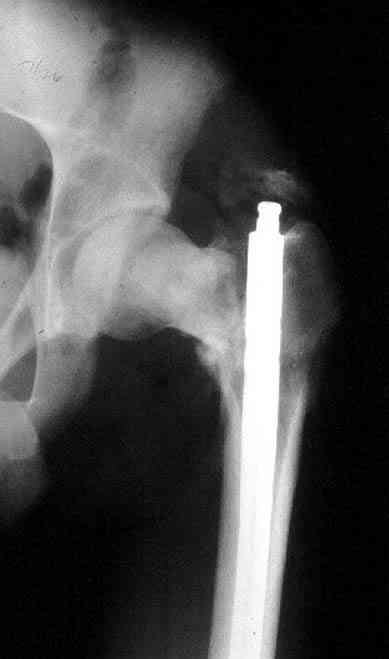

Несмотря на пессимистические прогнозы, у молодых

коррегирующая вальгусная остеотомия является более

приемлемым.

Представленные случаи доказательства тому, что еще

имеется резервы на восстановление даже у 5-6 месячных ложных суставов шейки.